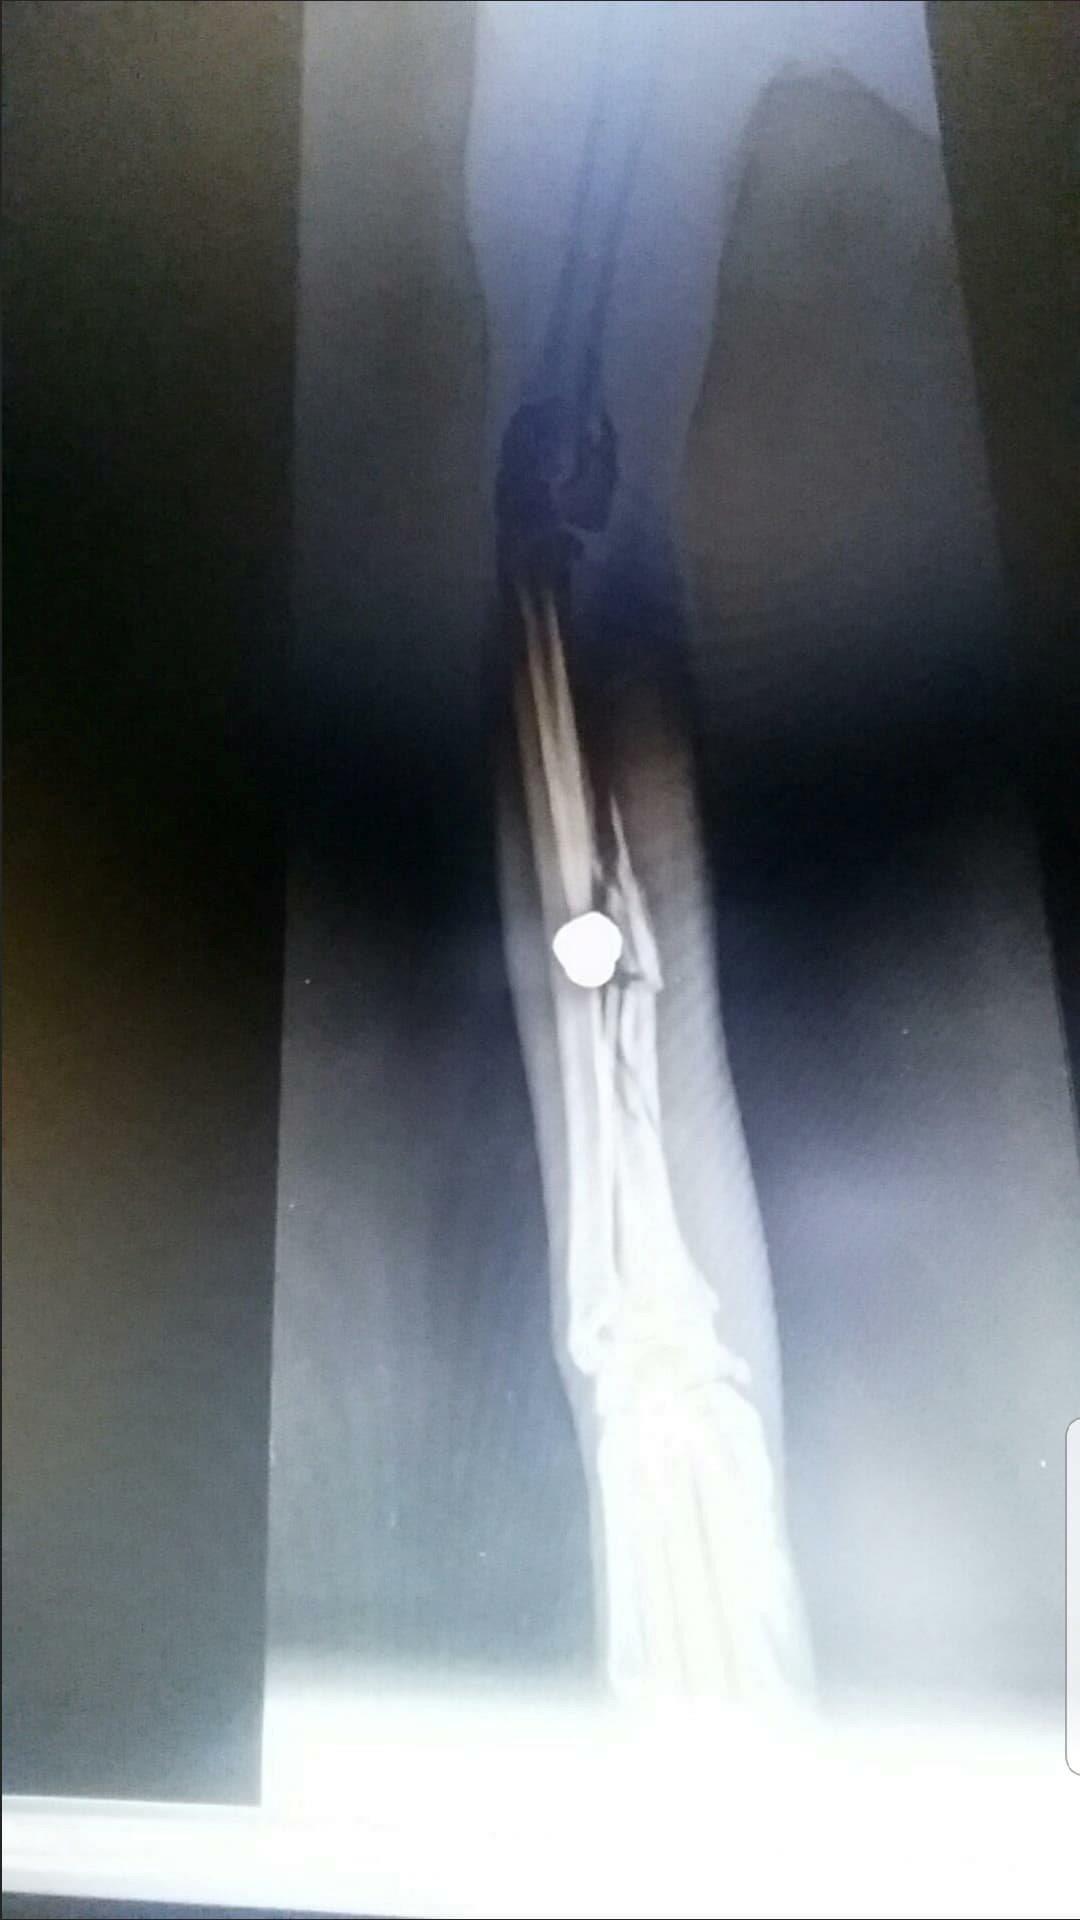

Gucci's mum has shared the x-rays with us.